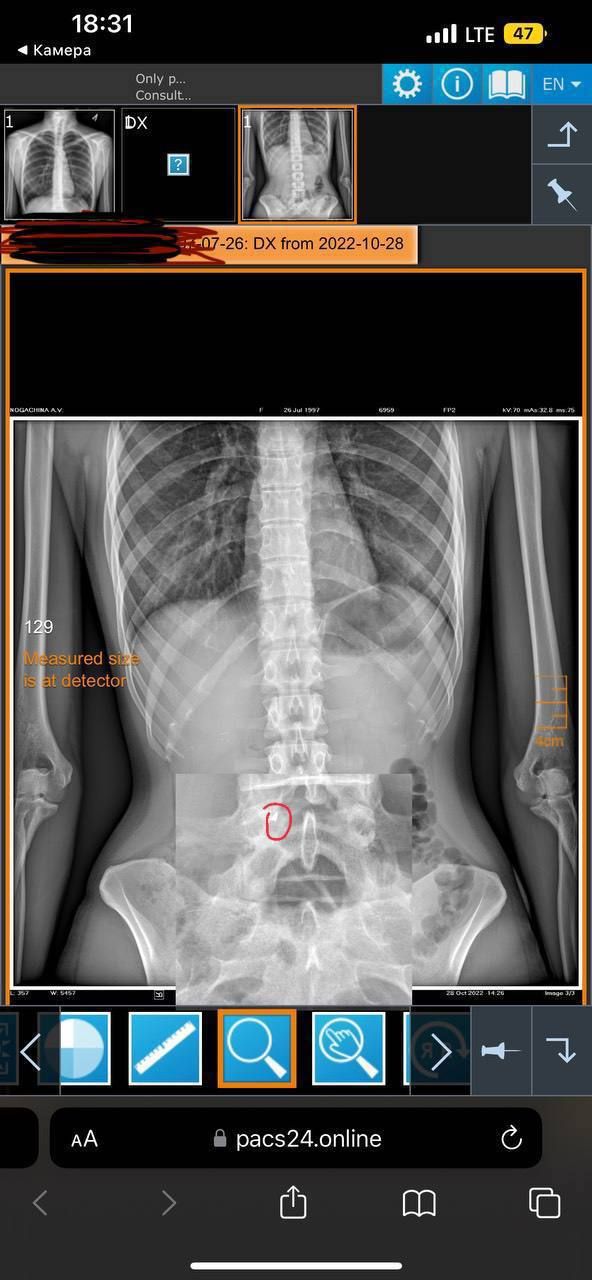

Коли подруга почала їсти батончик , то нажаль один з осколків вона проковтнула . Не одразу, але вона відчула біль та вирішила поїхати до лікарні та перевірити усе гаразд чи ні. Лікарі зробили огляд та рентген і виявили уламок (3 мм).